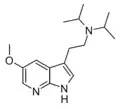

| Chemical structure | Short Name | Origin | Ring Substitution | RN1 | RN2 | Full Name | CAS Number |

|---|---|---|---|---|---|---|---|

| 5-MeO-NMT | Plants | 5-OCH3 | H | CH3 | 5-methoxy-N-methyltryptamine | 2009-03-2 |

| 5-MeO-DMT | Animals, plants | 5-OCH3 | CH3 | CH3 | 5-methoxy-N,N-dimethyltryptamine | 1019-45-0 |

| MiPT | artificial | H | CH3 | CH(CH3)2 | N-Methyl-N-isopropyltryptamine | 96096-52-5 |

| 5-MeO-MiPT | artificial | 5-OCH3 | CH3 | CH(CH3)2 | 5-methoxy-N,N-methylisopropyltryptamine | 96096-55-8 |